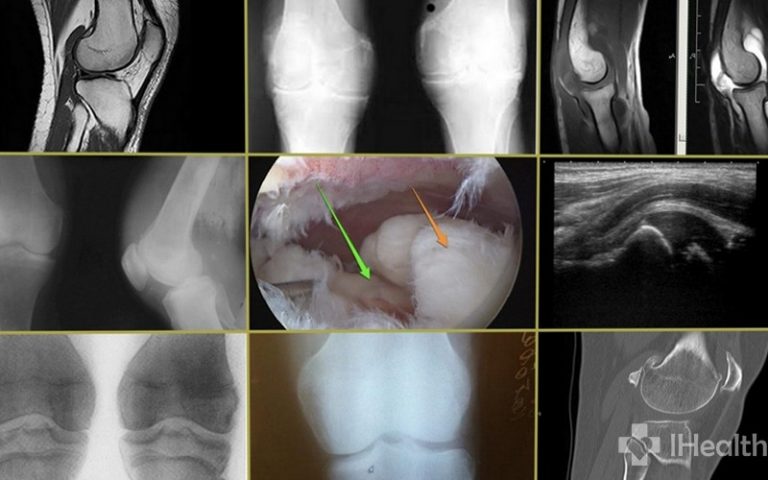

Синовіт колінного суглоба: причини, симптоми і 10 рецептів лікування

Синовіт колінного суглоба – це недуга, що полягає у виникненні …